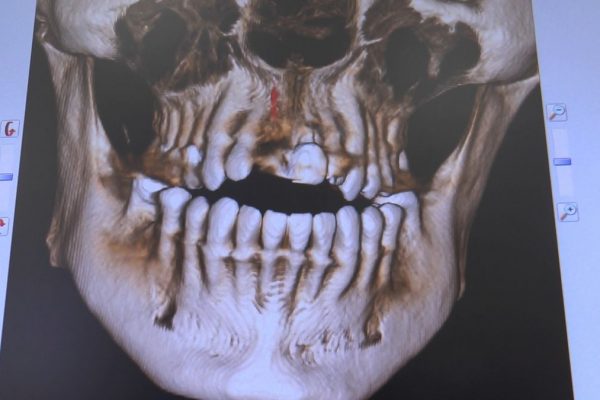

W ostatni weekend czerwca 2018 roku kursanci II Sezonu Preludium Implantologii odbyli piątą, finałową sesję, która w całości podporządkowana była praktyce. W ciągu dwóch dni zabiegowych Lekarze uczestniczący w szkoleniu przeprowadzili szereg zabiegów pod kierunkiem dr n.med. Violetty Szycik. Wszczepili 17 implantów oraz przeprowadzili ekstrakcje i zabiegi regeneracyjne kości. Zabiegi były wykonywane także w sedacji dożylnej z udziałem specjalisty anestezjologii i intensywnej terapii dr Jolanty Grzybowskiej. Preludium implantologii to nowy program edukacyjny dla adeptów implantologii stomatologicznej, którego celem jest wprowadzenie do implantologii poprzez pozyskanie wiedzy w szerokim zakresie i uwzględnieniem szczegółów mających decydujące znaczenie dla powodzenia leczenia implantologicznego. Ale tak jak wszystkie szkolenia w Instytucie Vivadental, w tym wiodące Practiculum Implantologii, zorientowane jest na praktyce i samodzielnym wykonywaniu zabiegów pod kierunkiem Mentora. To najlepsza edukacja w medycynie zabiegowej, a zarazem najlepszy start do implantologii.